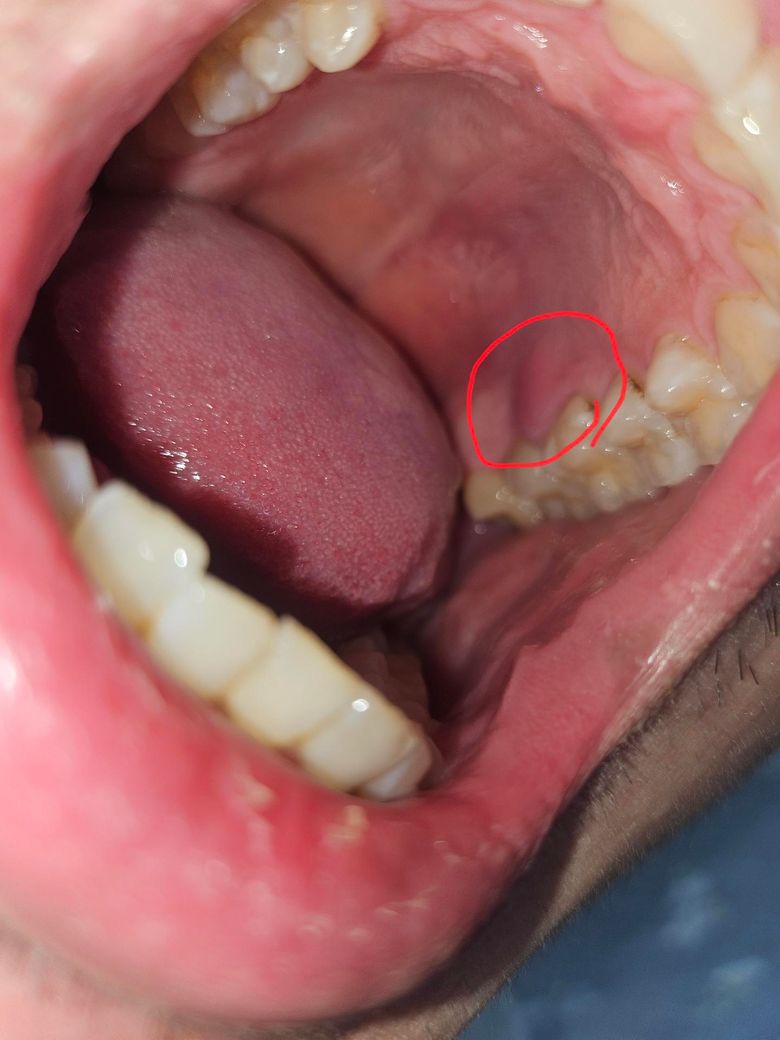

입안에 혹같은 게 났습니다 암인가요?

혀로 건드리다보니 표시와같이 부은거 같은 피부가 느껴져서요

먹을때 가끔 거슬리는 느낌과 살짝 통증이 느껴지네요.. 구강암일까요...

먹을때 가끔 거슬리는 느낌과 살짝 통증이 느껴지네요.. 구강암일까요... -> 악성병소의 양상으로 보이진 않습니다

사진으로 보이는 부분이 부어 있다면 잇몸 질환일 가능성이 높습니다. 잇몸에 염증을 유발할 수 있는 물질에 의해서 생기게 됩니다. 치아 내부의 신경으로 인한 염증이라면 신경치료가 필요할 수 있으며 치석등으로 인해서 생깁니다. 염증이라면 잇몸 치료가 필요할 수 있습니다. 구강암으로 보이진 않기 때문에 너무 걱정하지 않으셔도 될 것으로 생각됩니다.

자세한 확인을 위해서 치과에서 진료를 받아보는 것을 권유드립니다.